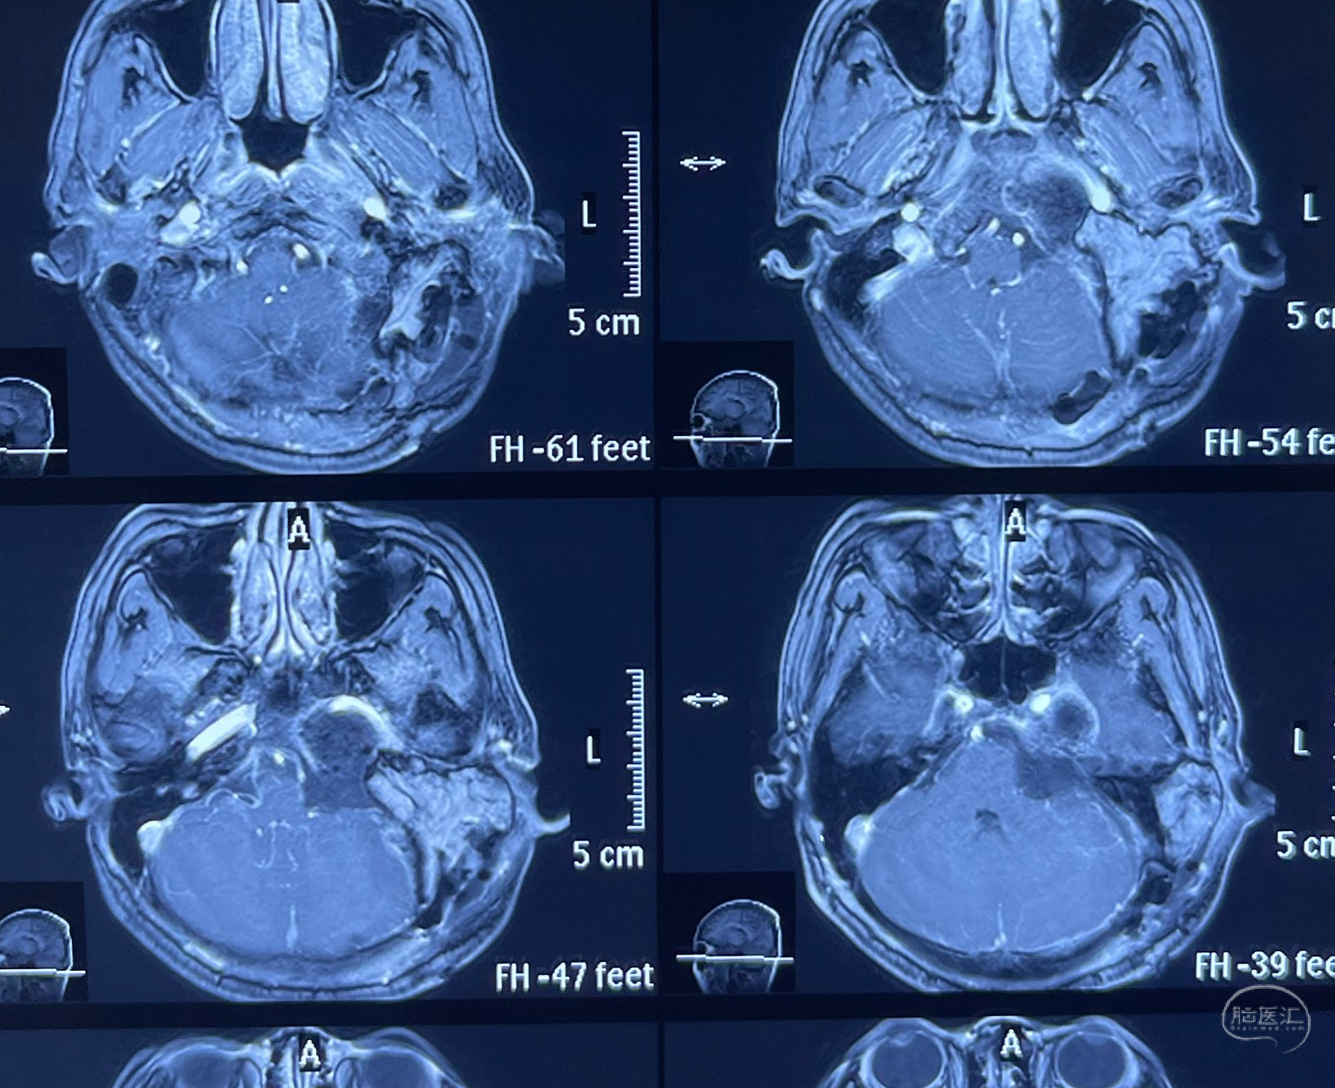

一个由颈静脉孔向上侵犯而来的肿瘤,岩骨基本被破坏,肿瘤已发展到颈内动脉岩骨段周围。对于这类肿瘤单从硬膜下去手术无论走中颅底还是后颅底乙状窦后都很难全切。对听力已经完全丧失的患者来说,其实是上帝给医生开了另一个窗户。曾经的经耳蜗入路就显得很好用了。当然游离并移位面神经岩骨垂直段是必修课。